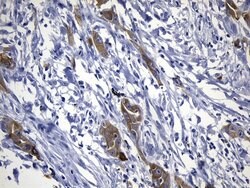

EGFR L858R Mouse anti-Human, Clone: UMAB234, lyophilized, UltraMAB™

EGFR (Epidermal growth factor receptor, HER1, ErbB1) is encoded by the EGFR gene located on chromosome 7 in humans. EGFR belongs to the HER/ERbB family of proteins that includes three other receptor tyrosine kinases, ERbB2, ERbB3, ERbB4. EGFR is a transmembrane receptor and binding of its cognate ligands such as EGF (Epidermal Growth Factor) and TGF alpha (Transforming Growth Factor alpha) to the extracellular domain leads to EGFR dimerization followed by autophosphorylation of the tyrosine residues in the cytoplasmic domain. Phosphorylation of EGFR at certain residues is also mediated by Src-non-receptor kinase. EGFR activation signals multiple downstream signaling cascades such as the Ras - ERK, PI3-K - Akt, Jak - STAT and PKC pathways that help in growth and proliferation of cells. Phosphorylation of EGFR at Y1086 specifically allows binding of the adaptor protein GRB2, leading to activation of the MAPK pathway. Upon receptor activation and signaling, EGFR is endocytosed and targeted for degradation or recycling. Mutations in the EGFR gene are associated with lung cancer and multiple alternatively spliced transcript variants encode different protein isoforms of EGFR have been found. Increased production or activation of EGFR has been associated with poor prognosis in a variety of tumors. Moreover, EGFR overexpression is observed in tumors of the head and neck, brain, bladder, stomach, breast, lung, endometrium, cervix, vulva, ovary, esophagus, stomach and in squamous cell carcinoma. This product is specific for EGFR (mutant L858R).Specifications

| Immunohistochemistry (Paraffin) | |

| Synthetic peptide around the L858R mutation region of the human EGFR conjugated to KLH | |